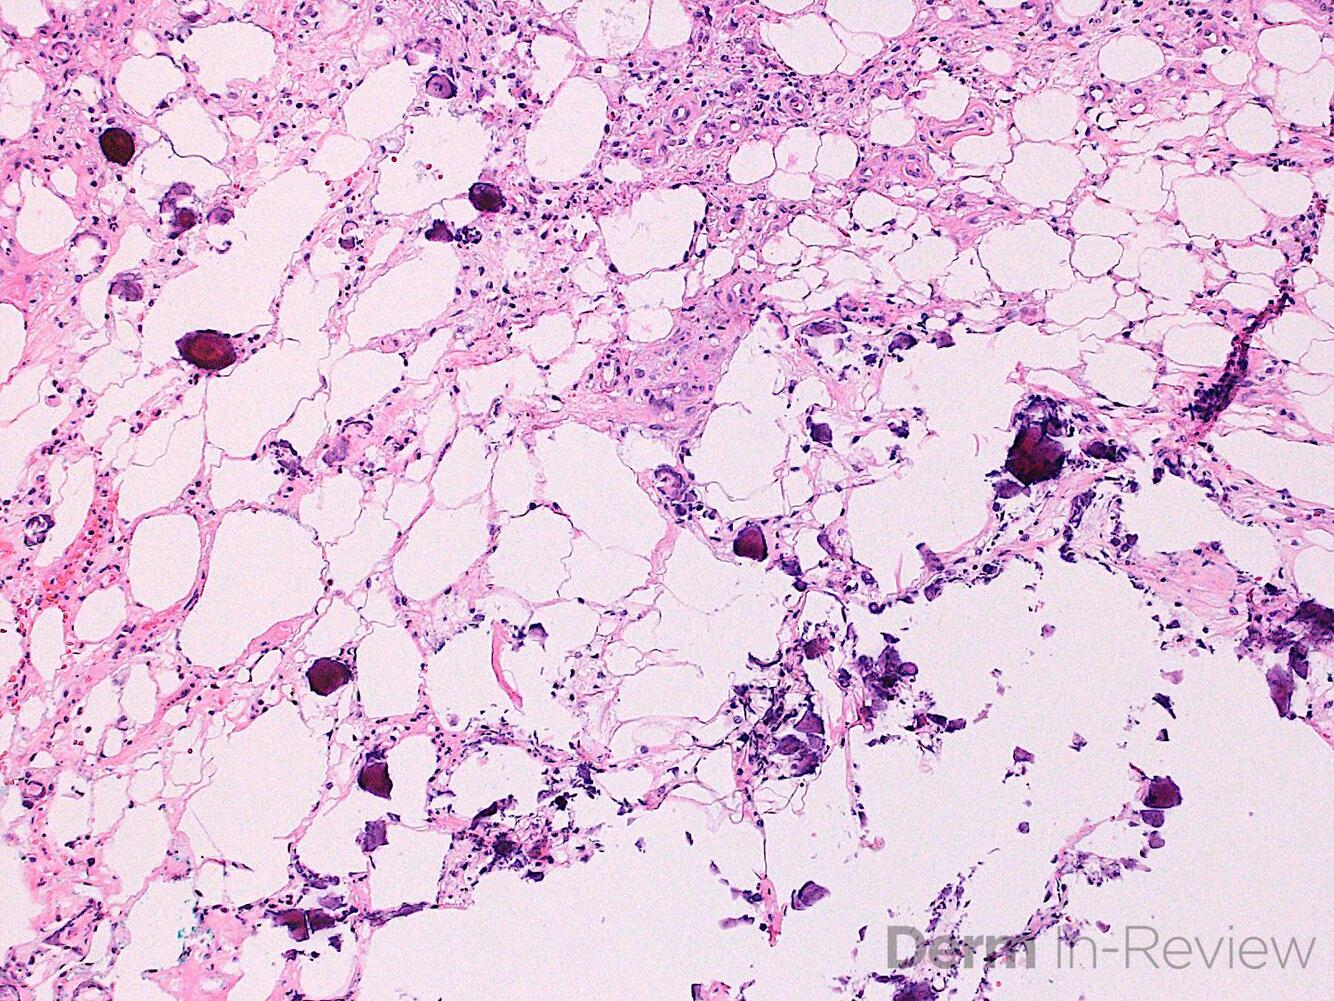

1. Which of the following is the most likely diagnosis of this image?

Correct choice:C. Metastatic adenocarcinoma

Explanation: In this image, the lymphatics are filled with large atypical cells trying to form glands making metastatic adenocarcionma the most likely diagnosis. Merkel cell carcinoma is a sheet of blue cells with salt and pepper nuclei. A lipoma is a collection of normal fat. Melanoma would have nests of atypical melanocytes. A myxoid neurothekeoma would be a loose collection of cells in thekes with a cellular stroma and the cells do not attempt to form glands.